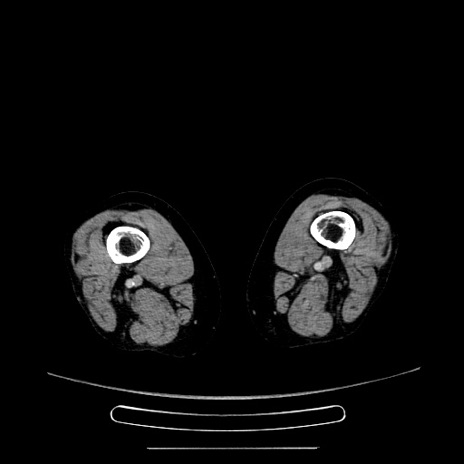

症例5(横断像)

【症例】70歳代女性

【主訴】お腹が張る

【現病歴】1週間くらい前から腹部膨満の自覚あり。昨日夜から増悪したため、本日救急外来受診。

【身体所見】意識清明、BT 36.5℃、BP 165/106mmHg、HR 80bpm、SpO2 98%、腹部:膨満、軟、自発痛・圧痛なし、触診にて不快感あり、腸蠕動音:減弱

【データ】WBC 12600、CRP 1.04